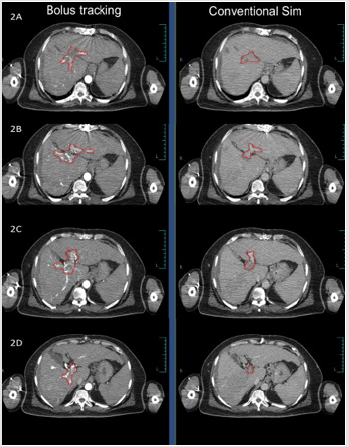

Target volume was better defined in arterial and portal phases after bolus tracking when compared to non-bolus tracked conventional contrast CT simulation scans (Figure 3). Imaging of liver is always facinating. Even in early CT scan era there was a concept of using contrast in phased manner to improve the contrast between liver parenchyma and tumour tissue [6,7]. Different dynamic scans use differential time gap between contrast infusion and scanning. Apart from the differential time gap, contrast flow rate and amount of contrast influence the image quality. Radiological diagnosis of the lesions were done mostly by the enhancement pattern in different phases and the architecture of the lesion. ‘Multiphasic’ CT scan for diagnosis of liver tumours are in use for last few decades. Multiphasic CT scan utilise the differential time gap between contrast infusion and image acquisition in arterial, venous or portal phase. Hepatic lesions are better visible in specific sequences, such as liver metastasis in arterial phase, primary liver tumour in venous phase and portal vein thrmobosis in portal phase. Liver parenchyma also uptake contrast. Differential contrast uptake between normal liver parenchyma and tumour defines the target volume.

Bolus tracking will improve the accuracy of tumour volume delineation and may reduce geographical miss as well as marginal recurrences. In summary, radiation oncologists consistently preferred arterial phase for better target volume delineation and portal venous phase for delineation of tumor thrombus in portal vein. ‘Bolus tracking’ method of contrast CT scan for tumour delineation provides appropriate target definition. In our experience with thirty-six primary liver tumours treated with ‘bolus tracking’ method during CT simulation have given appropriate deliniation of target. Our first two patients where target volume was compared with non-bolus and bolus tracking methods as well, there was a definitive better visualization of target volume with bolus tracking. Hence, in our institute bolus tracking is considered for all primary liver tumours. From our institutional experience we recommend bolus tracking with arterial phase for hepato cellular tumor delineation and portal venous phase for portal vein tumor thrombus delineation.